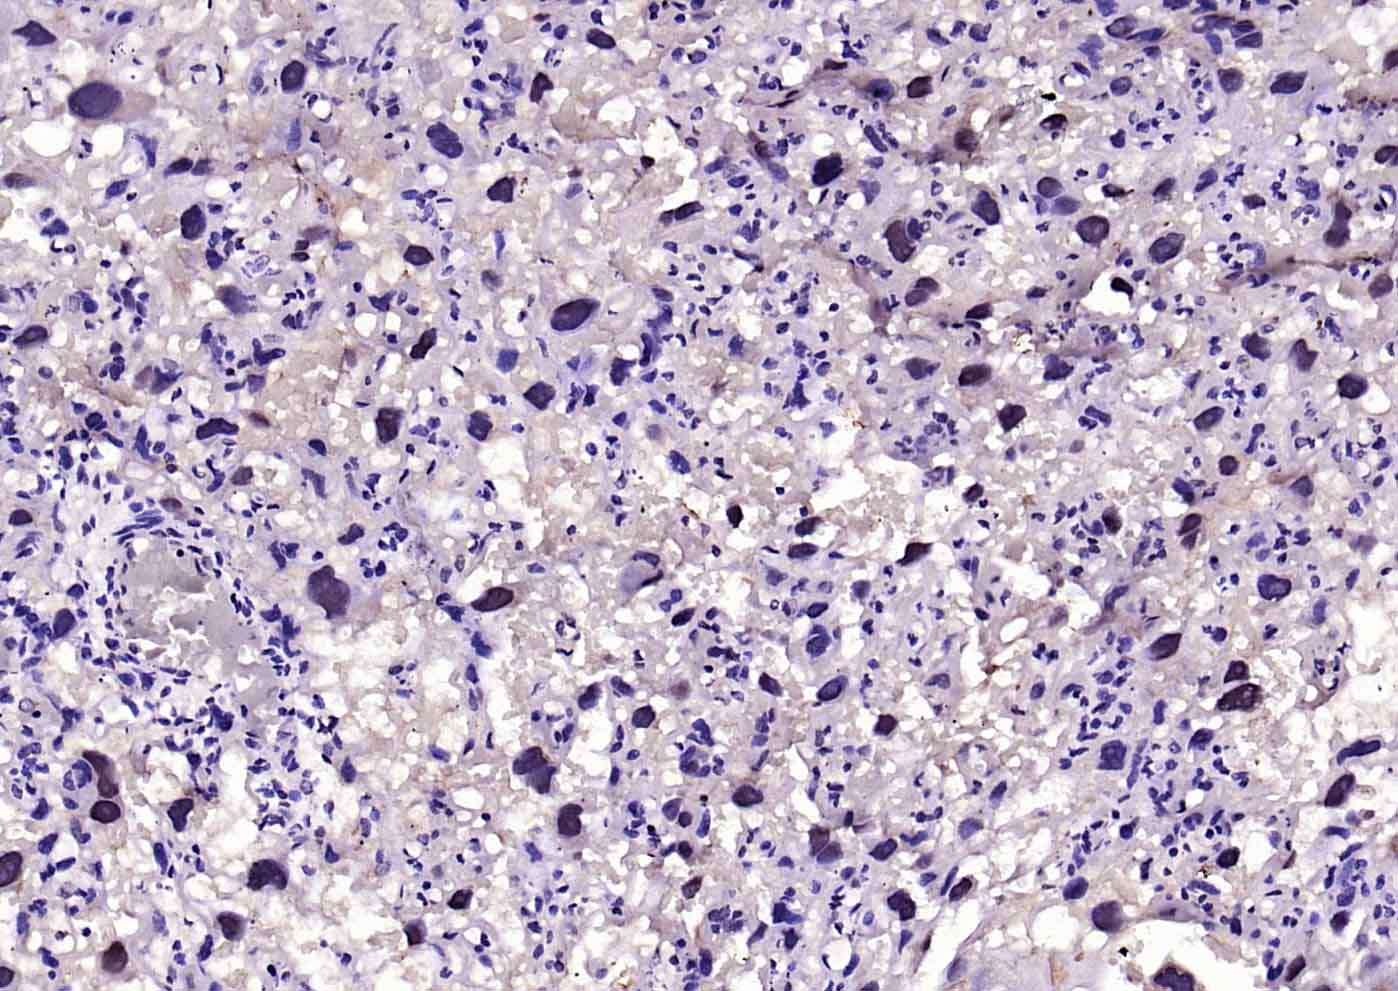

Paraformaldehyde-fixed, paraffin embedded (mouse kidney); Antigen retrieval by boiling in sodium citrate buffer (pH6.0) for 15min; Block endogenous peroxidase by 3% hydrogen peroxide for 20 minutes; Blocking buffer (normal goat serum) at 37°C for 30min; Incubation with (VEGFR3) Polyclonal Antibody, Unconjugated (bs-24954R) at 1:200 overnight at 4°C, followed by operating according to SP Kit(Rabbit) (sp-0023) instructionsand DAB staining.